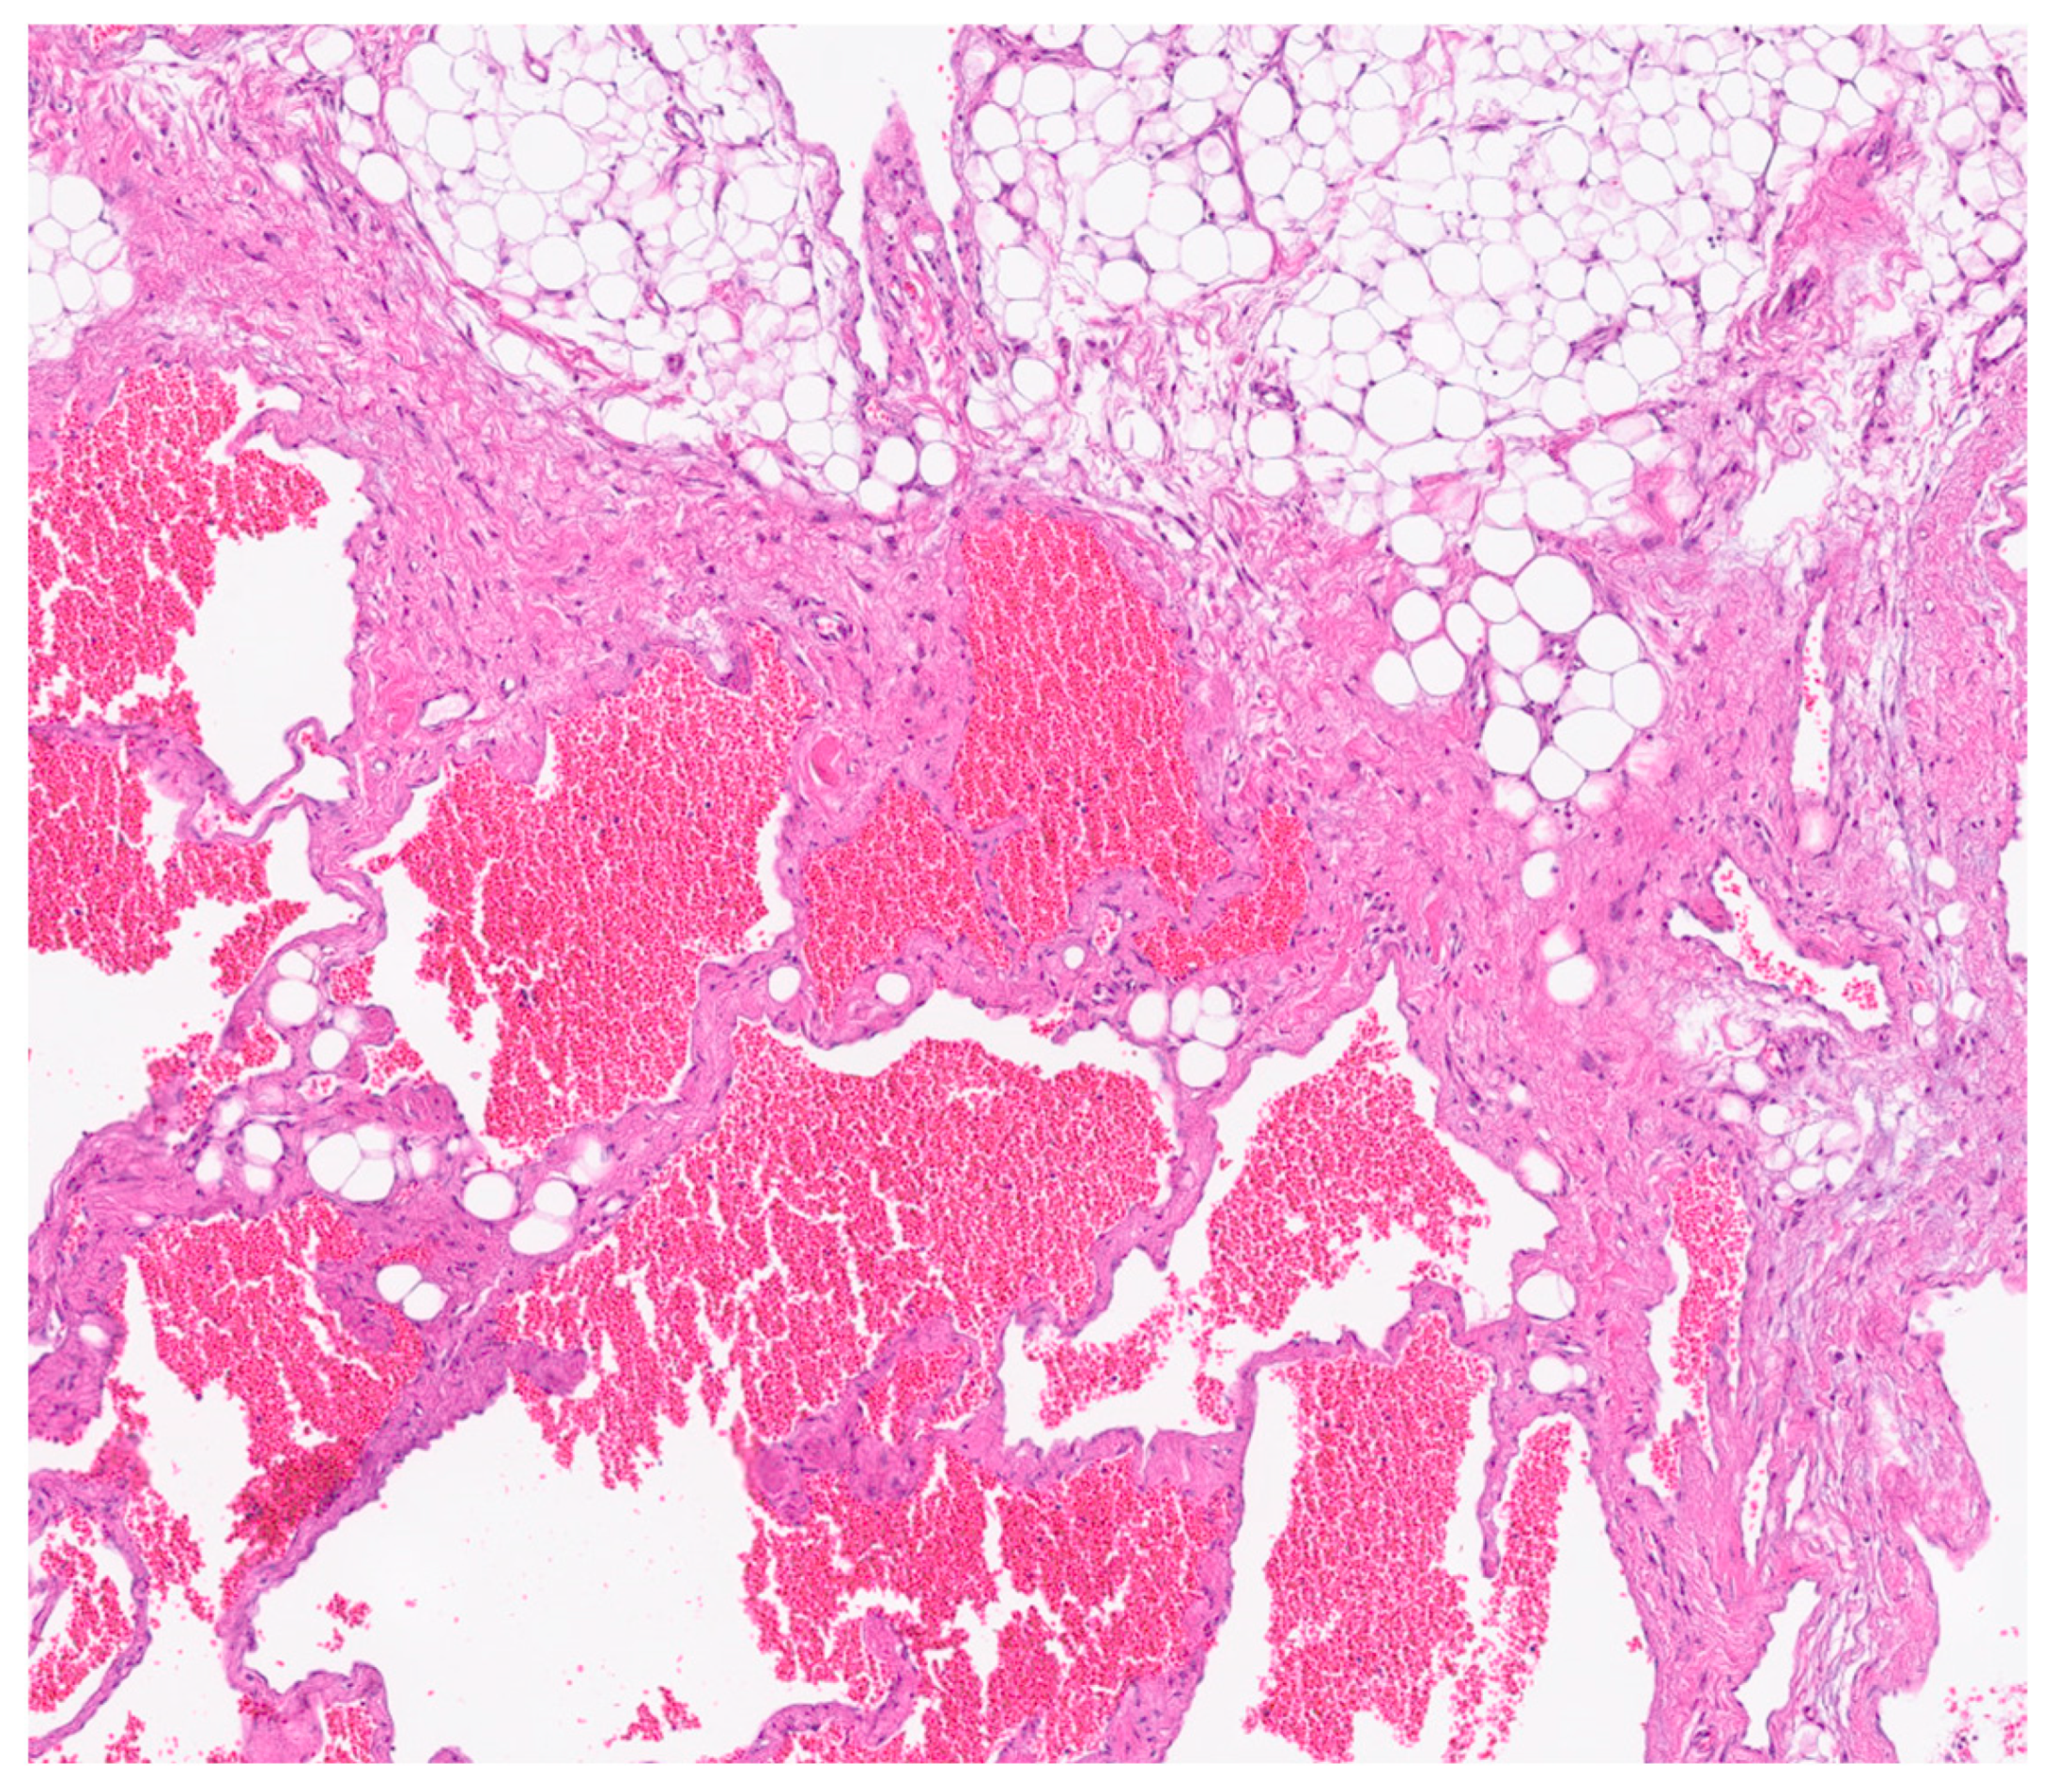

Figure 6. H&E-stained section shows the lesion is composed of variably sized anastomosing vascular spaces.

Immunohistochemical analysis revealed strong positivity for CD31, CD34, and podoplanin (D2-40), highlighting the coexistence of venous and lymphatic endothelial components [5]. This supported the final histological diagnosis of a combined lymphatic-venous malformation, in accordance with the 2018 ISSVA classification [4]. (Figure 6 and Figure 7).

Histological analysis revealed fibroadipose tissue containing smooth muscle elements and blood vessels, without significant cellular atypia. Cytological examination showed amorphous material, occasional pigment-laden macrophages, a moderate number of granulocytes, and a small fragment of fibroadipose tissue with sparse lymphocytic infiltration.

Postoperative pathological examination revealed a brownish, multiloculated cystic lesion measuring 18 × 17 × 30 cm, with areas of hemorrhage and multiple whitish calcified components. Subsequent analysis identified these calcifications as phleboliths, formed secondary to intralesional thrombotic events.